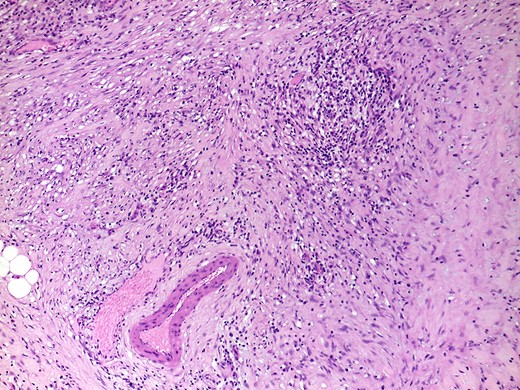

Two possibilities can be considered: one is that the patient had really type 1 AIP but in a burn-out stage and another is that the patient’s true diagnosis is an unclassified variant of AIP (mixed type 1 and 2 AIP). Not all cases of AIP fit clearly into the two subtypes. Some cases show the typical triumvirate histologic type 1 disease (i.e. dense lymphoplasmacytic inflammation, storiform-type fibrosis (Fig. 4), and obliterative phlebitis), but they also show more than an occasional intraductal aggregate of neutrophils. Others show typical type 2 disease pattern but with diffuse infiltrates of IgG4+ plasma cells, more than 50/high power filed (HPF) like in our case (Fig. 5). Dense, diffuse infiltrates of IgG4+ plasma cells that number >50/HPF are reportedly highly specific for IgG4RD [10], but definitive diagnosis of type 1 AIP should be based on the triumvirate histology. The absence of IgG4 cells does not necessarily imply the diagnosis of type 2, as type 1 also can be seronegative.

H&E, ×100. Parenchymal fibrosis with focal storiform-type areas and a lymphoplasmacytic infiltrate, that focally involves a vein, without overt obliterative phlebitis.

Focal areas with more than 50 IgG4+ plasma cells per high-power field were found, although a diffuse infiltrate was not present in this case.